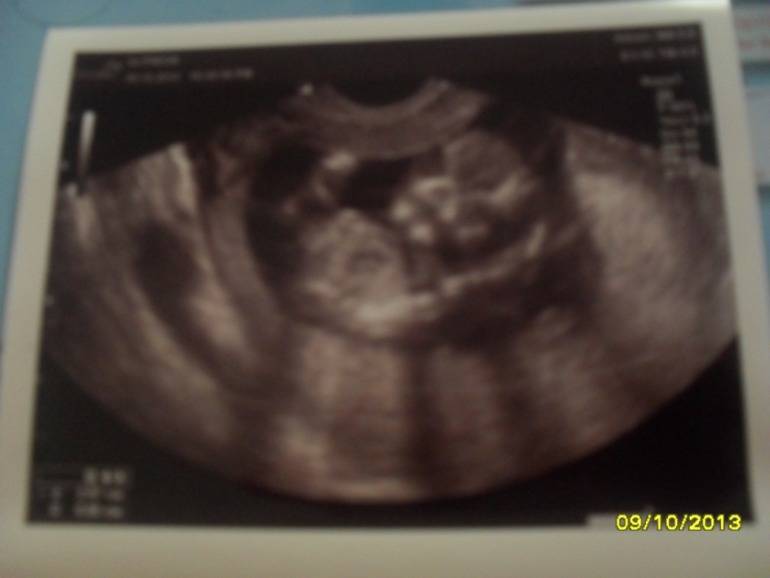

Первый скрининг!

Результаты: УЗИ, КТГ, доплера, скринингаСегодня мы были на первом скрининге.Пустили папу с нами,он увидел больше чем я!!!До сих пор под впечатлением.Малыш махал ему ручкой и закрывал личико.Всё у нас хорошо,КТР 72 мм.Нам 13 недель и 3 дня.Почти догнали акушерский срок,осталось 4 дня!И вот наше первое фото